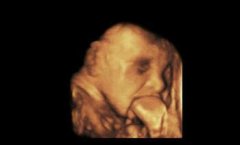

无脑儿

• 影视:孕妇产检找不到婴儿头,医生诊断无脑儿,只因怀孕前期做了这事

无脑儿 胎儿 叶酸 2024/11/27

• 孕妇产检找不到婴儿头,医生诊断是无脑儿,孕妇崩溃了

胡丽 无脑儿 孩子 2025/10/07